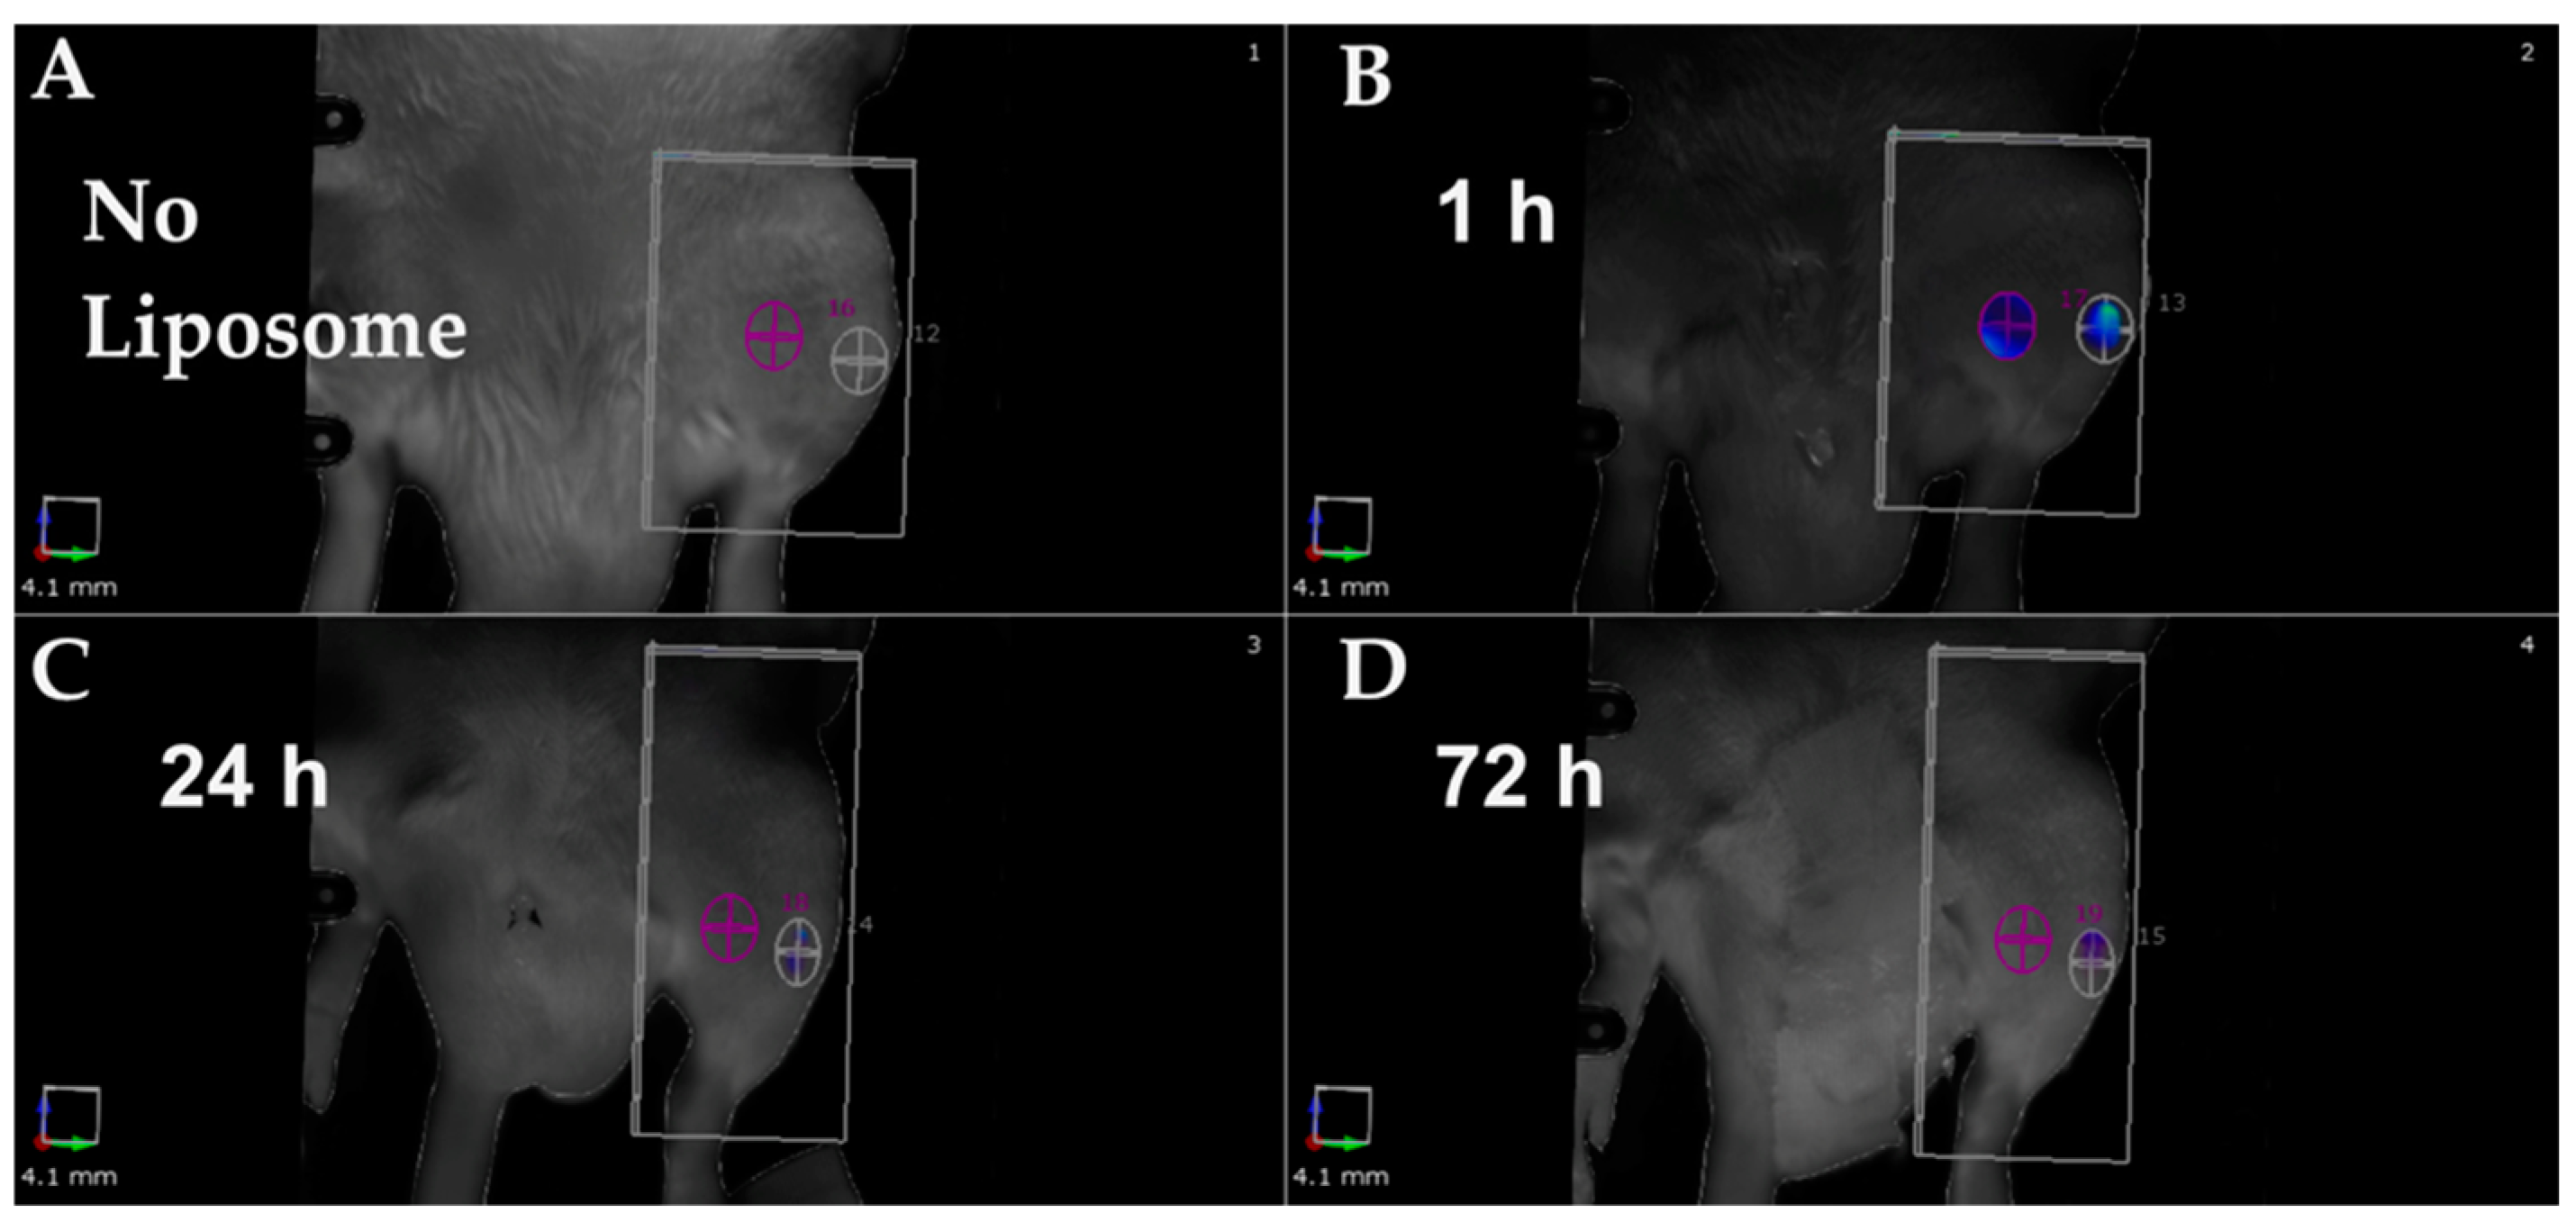

- Riyaz, S.; Helmholz, H.; Medina, T.P.; Medina, O.P.; Will, O.; Sun, Y.; Wiese, B.; Glüer, C.-C.; Willumeit-Römer, R. Exploring the Usability of α-MSH-SM-Liposome as an Imaging Agent to Study Biodegradable Bone Implants In Vivo. Int. J. Mol. Sci. 2023, 24, 1103. [Google Scholar] [CrossRef] [PubMed]